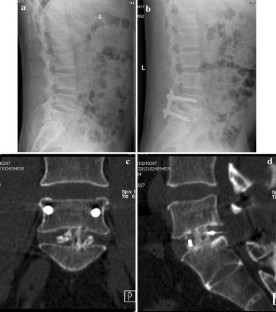

Fig. 2